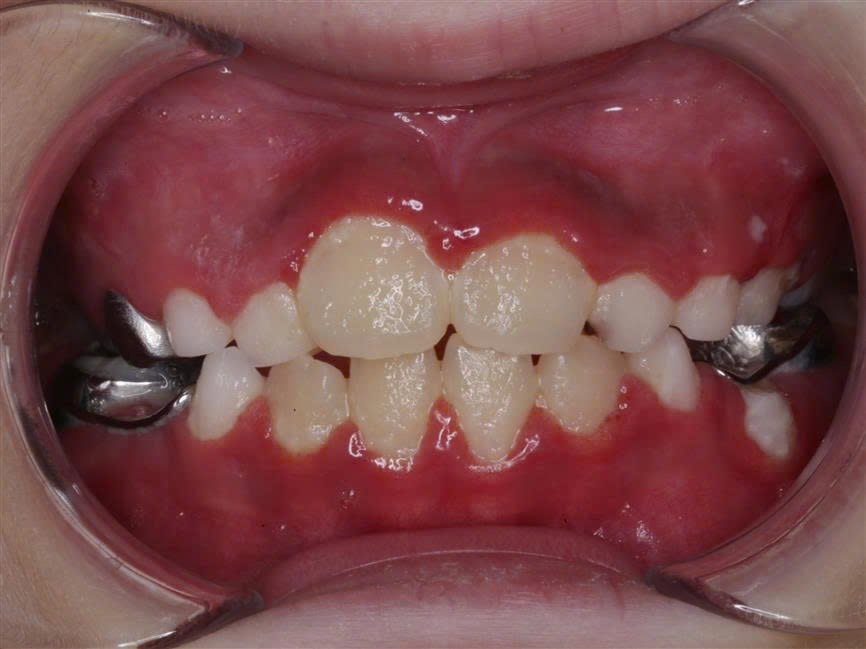

Tại sao răng hàm tự vỡ? – Cảnh báo từ tình trạng kém khoáng hóa men răng

Cảm giác răng mủn ra, tự vỡ dần, không hiểu vì sao” Đó là chia sẻ của không ít bệnh nhân đến thăm khám tại Nha khoa Như Ngọc, mang theo những chiếc răng hàm vỡ lớn một cách bất...